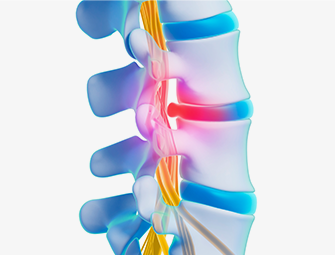

편안한 척추 관절 건강의 시작

오늘의 통증을 줄이고

내일의 건강을 지켜갑니다

원인 신경 차단

원인 신경 차단

실시간 영상 확인

실시간 영상 확인

빠른 통증 감소

빠른 통증 감소

빠른 일상생활 복귀

빠른 일상생활 복귀